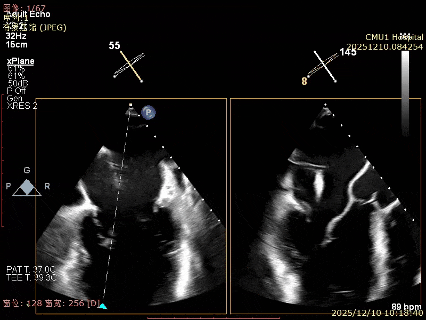

患者食道胃底静脉曲张,遂行TTE术前评估

术前TTE评估:

MR反流病因:DMR(部分腱索断裂)、Carpentier II型;

反流程度:极重度(5+),PISA法估测EROA约1.12cm²,R-VOL约98ml;

病变情况:P2-部分P3,脱垂宽度约27mm ,连枷间距11-13mm,瓣口面积7.8cm²,PML约25mm

其他:TR(重度) ,间接估测PASP约65mmHg;

预估手术难点:后叶冗长,脱垂宽度大,连枷间距大。